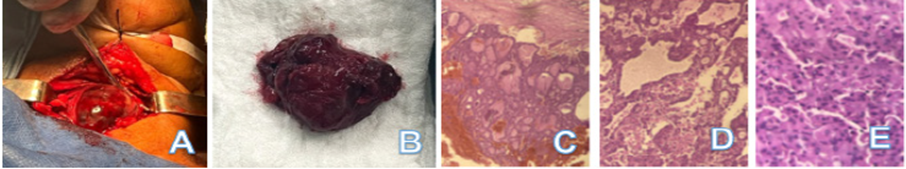

Paciente ingresó bajo diagnóstico de bocio multinodular a expensas de neoplasia de CH, planteándose conducta de tiroidectomía total, donde los hallazgos operatorios fueron: 1. Glándula tiroides de aproximadamente 7 x 6 cm, con nodulo con degeneración quística que abarca la totalidad de la misma. (Figura 2 A y B) 2. Nervio laríngeo superior y recurrente sin alteraciones. 3. Paquete vascular sin alteraciones.

Figura 2 A. Hallazgos operatorios. B. Pieza quirúrgica extraida. C y D. Microfotografías HE-10X. Se evidencian patrones de crecimiento folicular a expensas de células de Hurthle. E. Microfotografía HE-100X. Se evidencian células foliculares poligonales, con citoplasma granular ampliamente ocupado por mitocondrias y con núcleos hipercromáticos, características de células oncocíticas.

Paciente egresa a las 48 horas del postoperatorio. El estudio histopatológico reportó adenoma de CH encapsulado, de patrón predominantemente microfolicular con degeneración quística, sin criterios que sugieran malignidad (Figura 2 C-E). Actualmente en seguimiento por consulta externa, sin complicaciones.